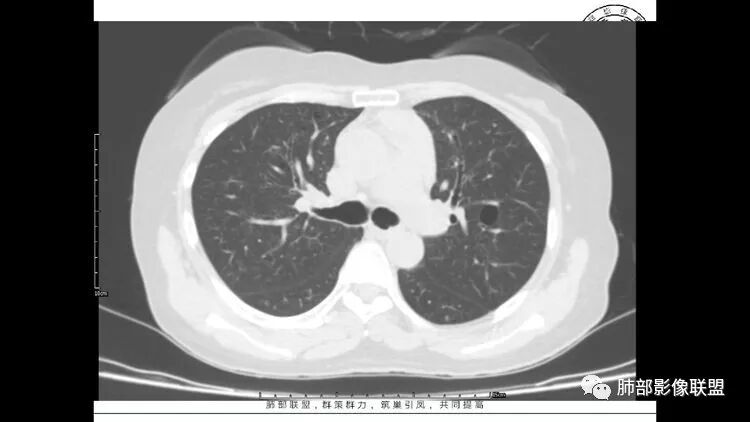

胸CT:1.双肺多发囊性变,以中下肺为主,病变边缘可见肺动脉,部分囊内可见分隔及肺动脉,双下部分肺野周围可见小叶中心结节及树丫征。

2 左肺上叶尖后段 右肺上叶前段 右肺下叶外基底段 结节影,边界清楚,可见柔软毛刺,左肺下叶后基底段混合密度影。

双肺多发磨玻璃结节,其内可见空腔,周围边界清晰,多发囊,左肺实性结节。考虑间质性肺炎,LIP可能性大。鉴别腺癌。

中年女性,双肺多发囊性变,以中下肺为主,病变边缘可见肺动脉,部分囊内可见分隔及肺动脉,左肺上叶较大结节,可见分叶、月牙铲,左肺下叶、右肺中叶磨玻璃病灶,边界清楚,内有空泡,结节,可见尖后段 右肺上叶前段 右肺下叶外基底段 结节影,边界清楚,纵隔淋巴结肿大,

1.左下肺腺癌;2.两肺弥漫性病变(多发囊腔、部分囊壁不规则,分布无特异,结节,空洞,树芽征,GGO),结合眼部情况首先考虑LIP,不典型感染(病毒或其他)待排。

双肺多发囊性病变,右下肺结节伴树芽,左上肺结节影,边缘清晰,毛刺。有类风湿,及眼干病史。考虑lip,腺癌。鉴别血管炎。

双肺多发磨玻璃结节病灶,内见实性成分及蜂窝,小泡征,考虑腺癌,淋巴瘤待排除,双肺多发肺气囊,沿支气管血管束分布,双肺多发小结节,部分小叶中心分布、部分位于胸膜下,边缘模糊,符合LIP,综合考虑LIP合并淋巴瘤或腺癌

双肺多发囊性变及结节影,囊壁光滑,结节部分为实性,边缘清,未见明显毛刺、胸膜牵拉及血管集束征象。双中下可见树芽。考虑淋巴细胞间质性肺炎,鉴别肺癌恶性病变。

双肺下叶分布为主的间质改变(磨玻璃影、小叶间隔增厚)、散在气囊影(常有血管贴边)、边界不清小结节